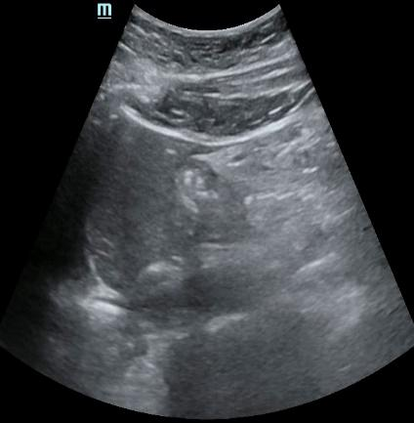

Most deep neural networks (DNNs) based ultrasound (US) medical image analysis models use pretrained backbones (e.g., ImageNet) for better model generalization. However, the domain gap between natural and medical images causes an inevitable performance bottleneck. To alleviate this problem, an US dataset named US-4 is constructed for direct pretraining on the same domain. It contains over 23,000 images from four US video sub-datasets. To learn robust features from US-4, we propose an US semi-supervised contrastive learning method, named USCL, for pretraining. In order to avoid high similarities between negative pairs as well as mine abundant visual features from limited US videos, USCL adopts a sample pair generation method to enrich the feature involved in a single step of contrastive optimization. Extensive experiments on several downstream tasks show the superiority of USCL pretraining against ImageNet pretraining and other state-of-the-art (SOTA) pretraining approaches. In particular, USCL pretrained backbone achieves fine-tuning accuracy of over 94% on POCUS dataset, which is 10% higher than 84% of the ImageNet pretrained model. The source codes of this work are available at https://github.com/983632847/USCL.